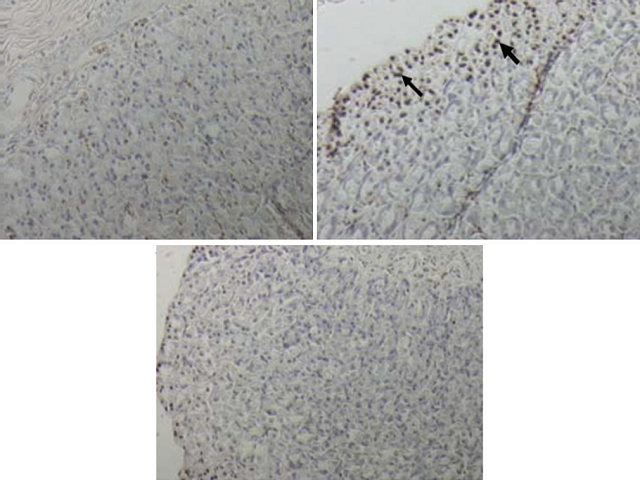

Aim: To study the effects of curcumin on Helicobacter pylori and N-methyl-N-nitrosourea (MNU)-induced gastric cancer in rats. Materials and Methods: Male Wistar rats were divided into three groups: control (CO), H. pylori inoculation and 30 ppm MNU in drinking water for 20 weeks (Hp + MNU), and H. pylori and MNU supplemented with 60 mg/kg curcumin for 30 weeks (Hp + MNU + Cur). The stomach was removed to examine nuclear factor kappa B (NF-κB) p65, 8-hydroxy-2'-deoxyguanosine (8-OHdG), cyclin D1, and Ki-67 in gastric epithelial cells by immunohistochemistry. The expression of apoptotic cells was measured by terminal deoxynucleotidyl transferase-mediated dUTP nick-end labeling reaction and gastric histopathology. Results: Two rats in Hp + MNU developed adenocarcinoma (ADC) of the glandular stomach (40% incidence, n = 5), while in Hp + MNU + Cur, no gastric ADC was found. Histopathology of gastric ADC showed the invasion of malignant cuboidal epithelial cells to submucosal layer. The percentages of NF-κB p65, 8-OHdG, cyclin D1, and Ki-67 immunoreactive cells in Hp + MNU compared with CO were 12.20% ± 1.10% versus 1.86% ± 1.49%, 13.21% ± 0.90% versus 2.84% ± 1.29%, 66.96% ± 5.91% versus 6.06% ± 6.48%, and 42.29% ± 0.08% versus 14.95% ± 0.12%, P < 0.05, respectively. The expression of apoptotic cells significantly increased in Hp + MNU compared with CO (8.41% ± 0.01% vs. 0.53% ± 0.02%, P < 0.05). Curcumin supplementation reduced the gastric cancer incidence compared with Hp + MNU. Percentages of NF-κB p65, 8-OHdG, cyclin D1, and Ki-67 immunoreactive cells in Hp + MNU + Cur compared with Hp + MNU were 4.76% ± 3.73% versus 12.20% ± 1.10%, 1.76% ± 0.94% versus 13.21% ± 0.90%, 24.71% ± 4.62% versus 66.96% ± 5.91%, and 24.99% ± 0.05% versus 42.29% ± 0.08, P < 0.05, respectively. The apoptosis expression was significantly improved (4.14% ± 0.16% vs. 8.41% ± 0.01%, P < 0.05). Conclusion: Curcumin can reduce gastric cancer incidence induced by H. pylori infection and MNU administration through the suppression of key proteins and apoptosis involved in carcinogenesis.